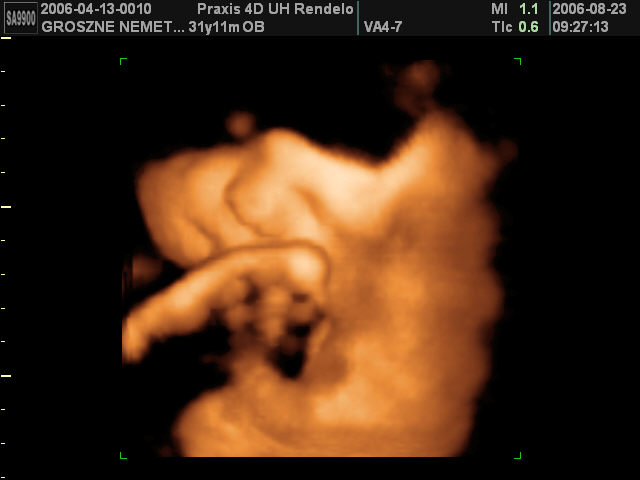

Ultrahang képek 36 hetes korban, naggyon jóóó!:

Amikor először láttam ezt a 4D-st, elájultam. Annyira brutálisan élethű, hogy hihetetlen...:)